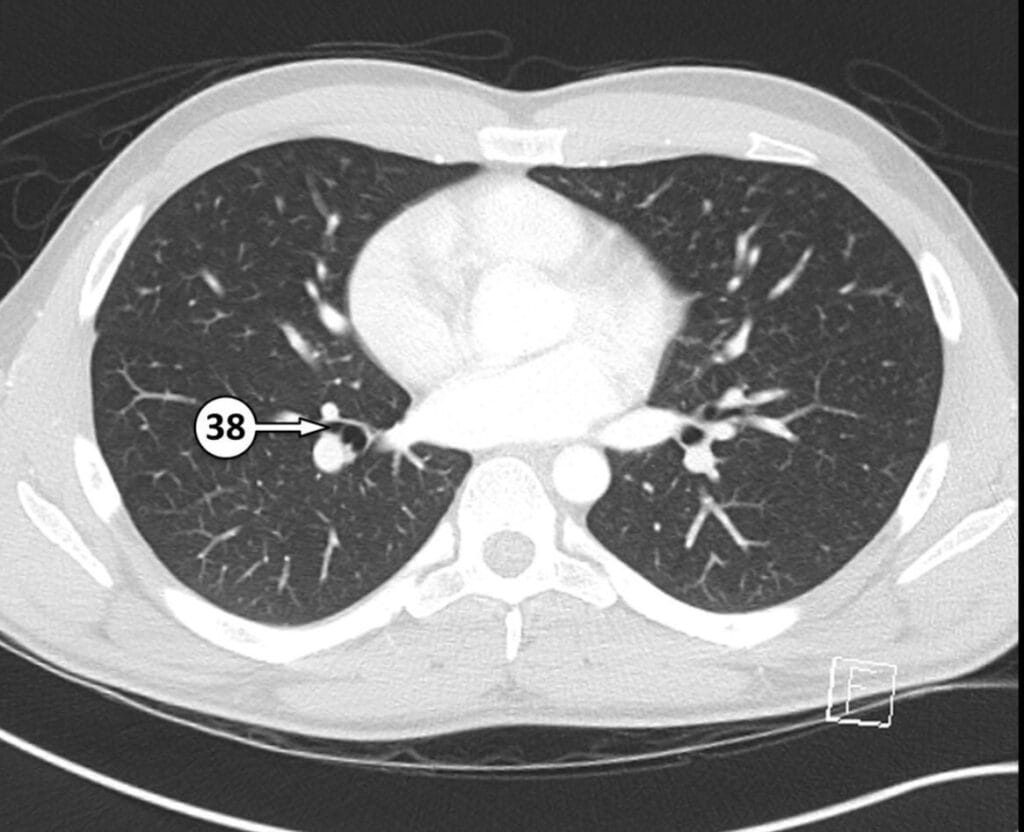

38. lateral basal segmental bronchus of RLL